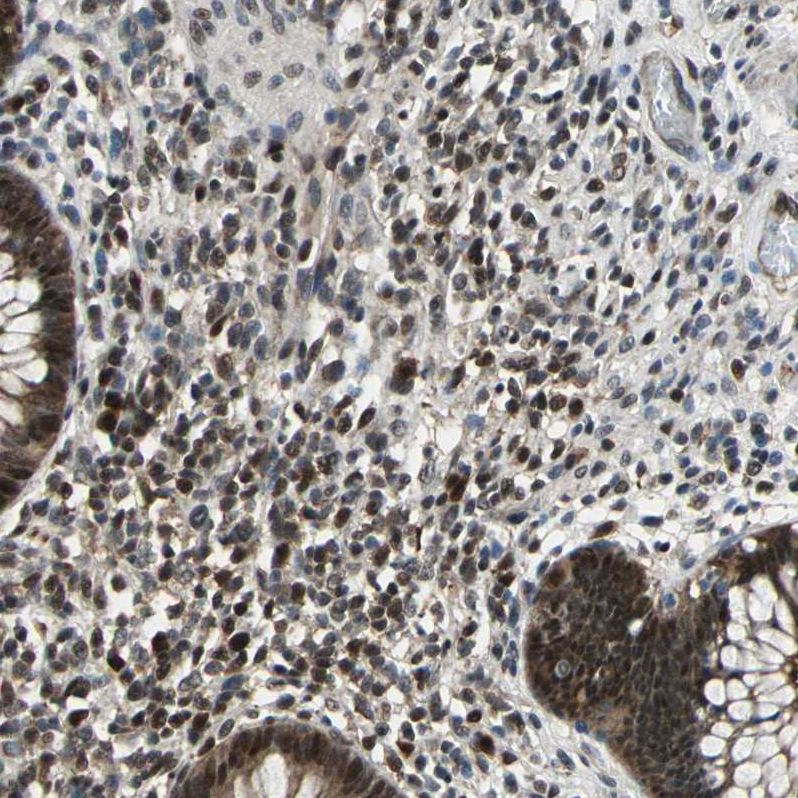

Immunohistochemical staining of human rectum shows moderate nuclear positivity in lymphoid cells.